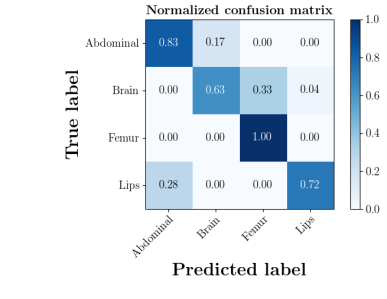

We further compare the performance of MIDNet in a semi-supervised setting and a fully-supervised setting. Here, the semi-supervised setting utilizes the training data containing labeled data and unlabeled data, while the fully supervised setting only uses the labeled data. The confusion matrix in Fig. 14 shows the effectiveness of unlabeled data in our proposed method, for example, the classification accuracy of greatly improves when integrating unlabeled data (semi-supervised).

| With unlabeled data | Without unlabeled data |

|

|